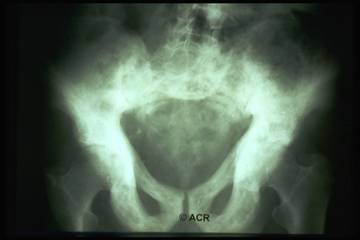

Malattia di Paget

Disordine dell'osso unifocale o multifocale con osteoporosi irregolare accompagnata da neoformazione ossea;

Spesso asintomatica - modificazioni radiografiche;

Reperti radiografici

Lisi ossea: riflette l'aumentata attività osteoclastica;

Sclerosi: riflette l'aumentata attività osteoblastica;

Aumento volumetrico dell'osso;

Lesioni litiche a "fiamma": riscontrabili a carico delle ossa lunghe;